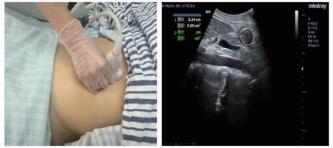

1.3 CT计算胃残余量和超声测定胃窦截面积⑴CT计算胃残余量:使用64排128层4D螺旋CT机(SOMATOM Definition AS型,德国SIEMENS公司)进行腹部CT检查,然后利用VOLUME-Work Flow医学图像软件(德国SIEMENS公司)对CT图像进行分析,即以Freehand方式对胃进行描记,从胃底开始逐层勾画胃壁轮廓形态并进行修正,以及设置CT评估限值,最终通过软件自动计算出胃腔总容积、胃腔气体容积、胃腔非气体容积及胃腔容积高度,其中胃腔非气体容积为患者胃残余量值(见图 1)。

| 图 1 CT检测胃容积的方法(左:描计胃轮廓;右:胃残余量计算) Fig 1 The capacity of stomach measured by CT (Left, the tracing of gastric outline; Right, the calculation of gastric residual volume) |

⑵超声测定截面积:由一位接受过急危重症超声规范培训的医师完成。使用M9便携式彩色多普勒超声诊断仪(深圳迈瑞公司),选择低频曲阵探头、频率2~5 MHz、标准腹部模式,患者分别于半坐位、平卧位与右侧卧位三种体位,探头置于上腹部矢状位或旁矢状位扫描,以腹主动脉、肠系膜上动静脉为定位标志获取胃窦图像,应用自由追踪描记技术描记胃窦截面的轮廓范围,取三次测量数据的平均值后计算胃窦截面积(见图 2)。

| 图 2 床旁超声检测胃窦截面积的方法(左:探头位置;右:胃窦截面轮廓描记) Fig 2 The cross-sectional area of gastric antrum measured by bedside ultrasound (Left, probe position; Right, outline tracing of gastric antrum cross-section) |